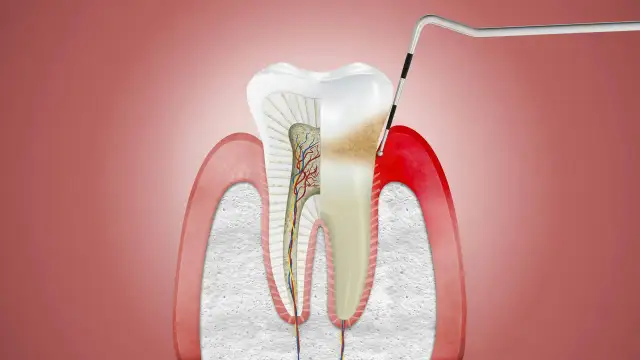

Dowiedz się, jak pozbyć się ropy z dziąseł i uniknąć poważnych komplikacji zdrowotnych. Sprawdź skuteczne metody i ważne informacje na ten temat.